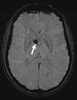

Subependymal giant cell astrocytoma

Subependymal giant cell astrocytoma (SEGA, SGCA, or SGCT) is a low-grade astrocytic brain tumor (astrocytoma) that arises within the ventricles of the brain. It is most commonly associated with tuberous sclerosis complex (TSC). [Source: Wikipedia ]